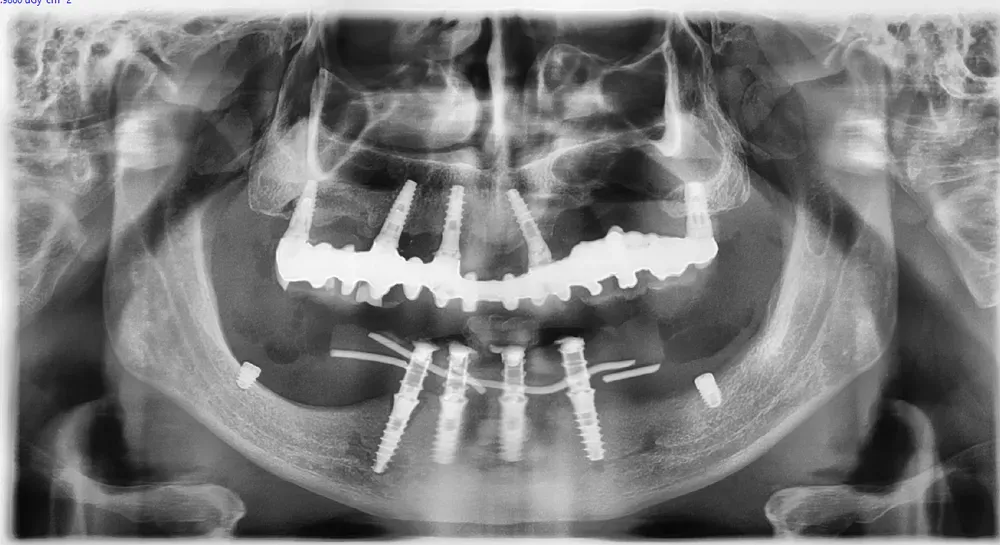

Personalmente, amo scegliere il numero e le misure degli impianti in base alle caratteristiche anatomiche del singolo paziente, piuttosto che affidarmi a protocolli troppo rigidi e standardizzati. Sempre nell’ottica della rigenerazione su misura, ritengo che ogni caso debba essere studiato individualmente per ottimizzare il risultato finale.

Le immagini radiografiche che seguono testimoniano alcune delle tante soluzioni tecniche che ho utilizzato per le arcate a carico immediato nel corso della mia carriera. Ogni caso presenta sfide diverse e richiede un approccio personalizzato.

Anche nei pazienti anziani con protesi mobili (dentiere) che presentano condizioni critiche dal punto di vista osseo, gli interventi di implantologia a carico immediato possono essere portati a termine con successo.

Tutto dipende dalle condizioni di salute generale e dall’anatomia residua. Non esiste un limite di età assoluto, ma solo una valutazione attenta del rapporto rischio-beneficio per ogni singolo paziente.